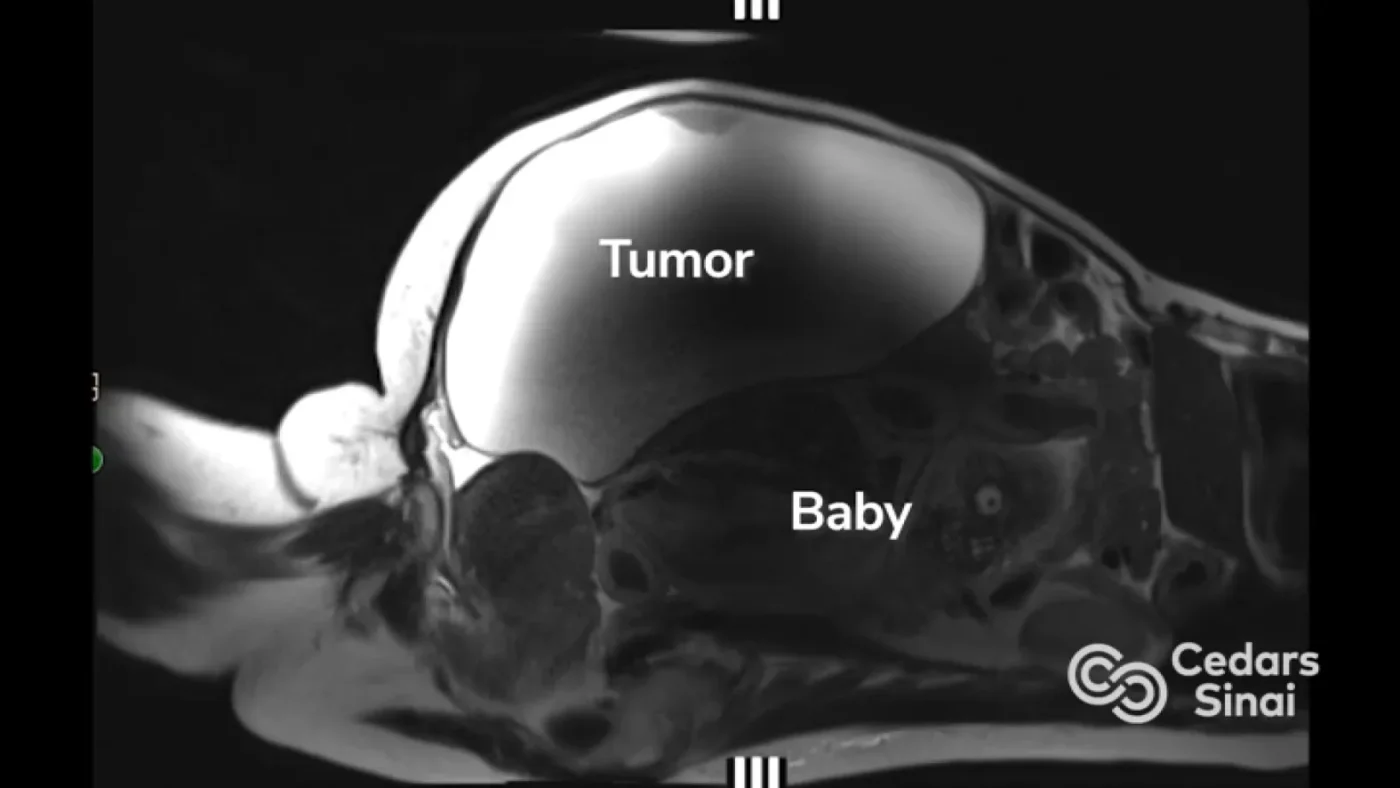

He wasn’t supposed to be here. Experts say babies like Ryu Lopez don’t usually make it this far. But this holiday season, the Lopez family is deeply grateful for beating incredible odds in what Cedars-Sinai physicians are calling a medical miracle.

Suze Lopez, a nurse from Bakersfield, California, was scheduled to finally have a 22-pound ovarian cyst removed; one that had been growing for years. But the results of a routine pregnancy test that was required before the surgery would give her the shock of a lifetime.

“Because of the large ovarian cyst that had been growing for years, it could have been a false positive, even ovarian cancer,” Lopez said. “And I was used to very irregular periods and some abdominal discomfort. I could not believe that after 17 years of praying, and trying, for a second child, that I was actually pregnant.”

Ozimek was stunned by what the diagnostic images revealed: a very rare abdominal ectopic pregnancy.

“Suze was pregnant, but her uterus was empty, and a giant benign ovarian cyst weighing over 20 pounds was taking up so much space,” Ozimek said. “We then discovered a nearly full-term baby boy in a small space in the abdomen, near the liver, with his butt resting on the uterus. A pregnancy this far outside the uterus that continues to develop is almost unheard of.”

Ozimek said that as the baby grew inside Lopez’s abdomen, behind the mass, it pushed the very large cyst forward. “It makes sense that she just thought the tumor was getting bigger again, not that she could be pregnant.